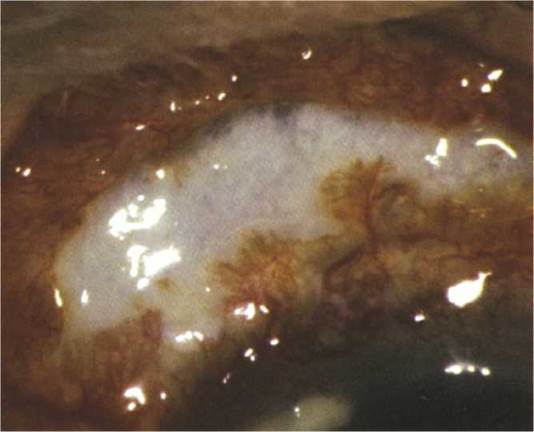

Other. Superior corneal “shield” ulcer (a well-delineated, sterile, graywhite infiltrate with overlying epithelial defect), limbal raised white dots (Horner-Trantas dots) of degenerated eosinophils (see Figure 5.1.7), and superficial punctate keratopathy (SPK).

FIGURE 5.1.7 Vernal/atopic conjunctivitis with raised white dots of eosinophils along limbus.